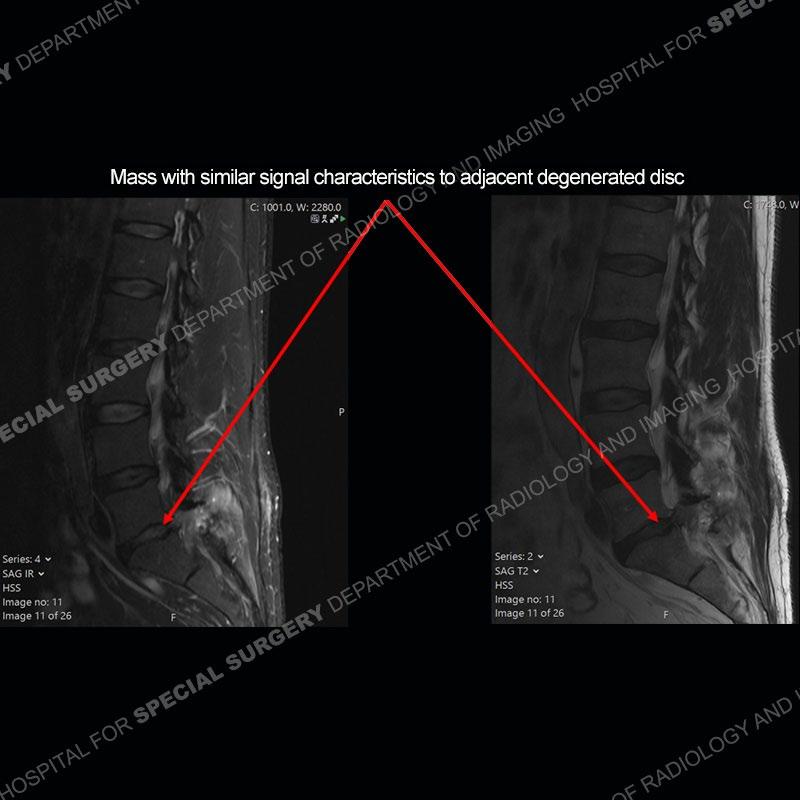

Post operative changes are seen on the left side at L5-S1 where there is near complete removal of the left sided L5 lamina, partial resection of the left L5-S1 facet joint, and resection of the left sided ligamentum flavum. In the anterolateral epidural space about the subarticular recess is a mass that demonstrates similar T1 and T2 signal characteristics to the adjacent degenerated disc. There is enhancement about the periphery of the mass, but the majority of this somewhat geographic or polyploid mass demonstrates no enhancement. The mass exerts prominent mass effect on the left S1 axillary sleeve/proximal nerve root. The left S1 nerve root shows enlargement and increased enhancement as compared to the contralateral right side.

Not as much of a diagnostic dilemma as some other cases but more so just a very nice example of what can be a difficult assessment at times. The evaluation of granulation tissue/scar/epidural fibrosis vs. disc herniation particularly in the earlier post operative period can be very difficult. Clues that can assist in identifying a disc herniation are a more geographic or polypoid nature to the mass, signal characteristics similar to the adjacent degenerated disc, mass effect upon the thecal sac/adjacent neural structures, and a typical enhancement pattern. As the disc material is avascular, as long as imaging is performed in a relatively rapid fashion after contrast administration (within 20-30 minutes), the granulation tissue around the disc will enhance but the disc material itself will not. If there is a marked delay between contrast administration and imaging, there may be diffusion of contrast into the disc making the assessment very difficult. The marked utility of contrast to help delineate disc vs. scar has led to our institution employing contrast fairly uniformly within the first two years following surgery.